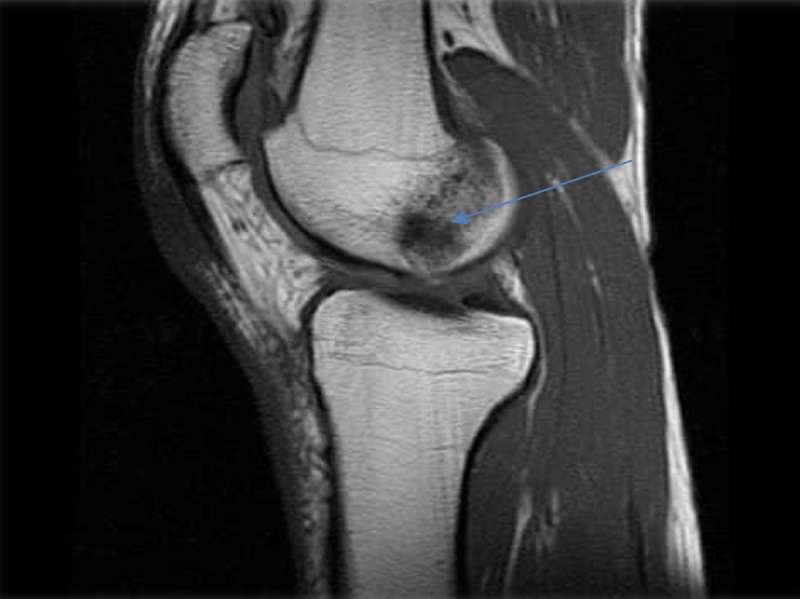

En la siguiente imagen podemos ver en Resonancia Magnética de rodilla, un edema óseo en el cóndilo femoral.